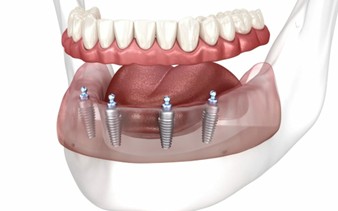

Dental implants are artificial tooth roots made from biocompatible titanium that are placed into the jawbone to support replacement teeth such as crowns, bridges, or dentures. They look, feel, and function just like natural teeth.

Implants fuse with the jawbone through a process called osseointegration, making them extremely stable and durable. This is why implants are considered the gold standard for replacing missing teeth.